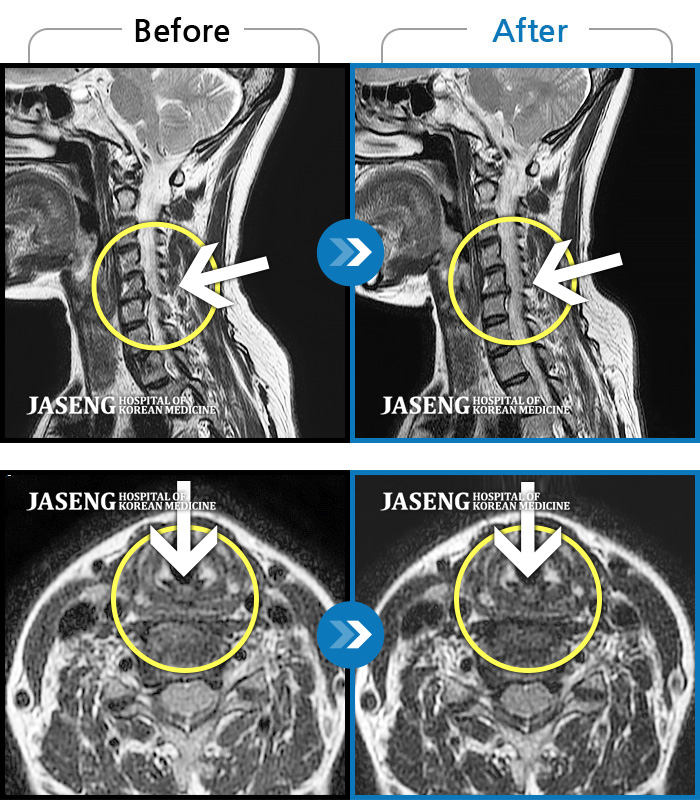

목디스크

도움받은 사례

인천 · 강아현 원장

처음 내원시 목에서 등으로 이어지는 통증 및 우측 팔 저림 증상이 심했고, 약간의 근력저하도 동반되어 일상생활이 어려운 상태였습니다.

촬영시기

2024.04.06 ~ 2024.11.16

2024.11.22

조회수 17,045